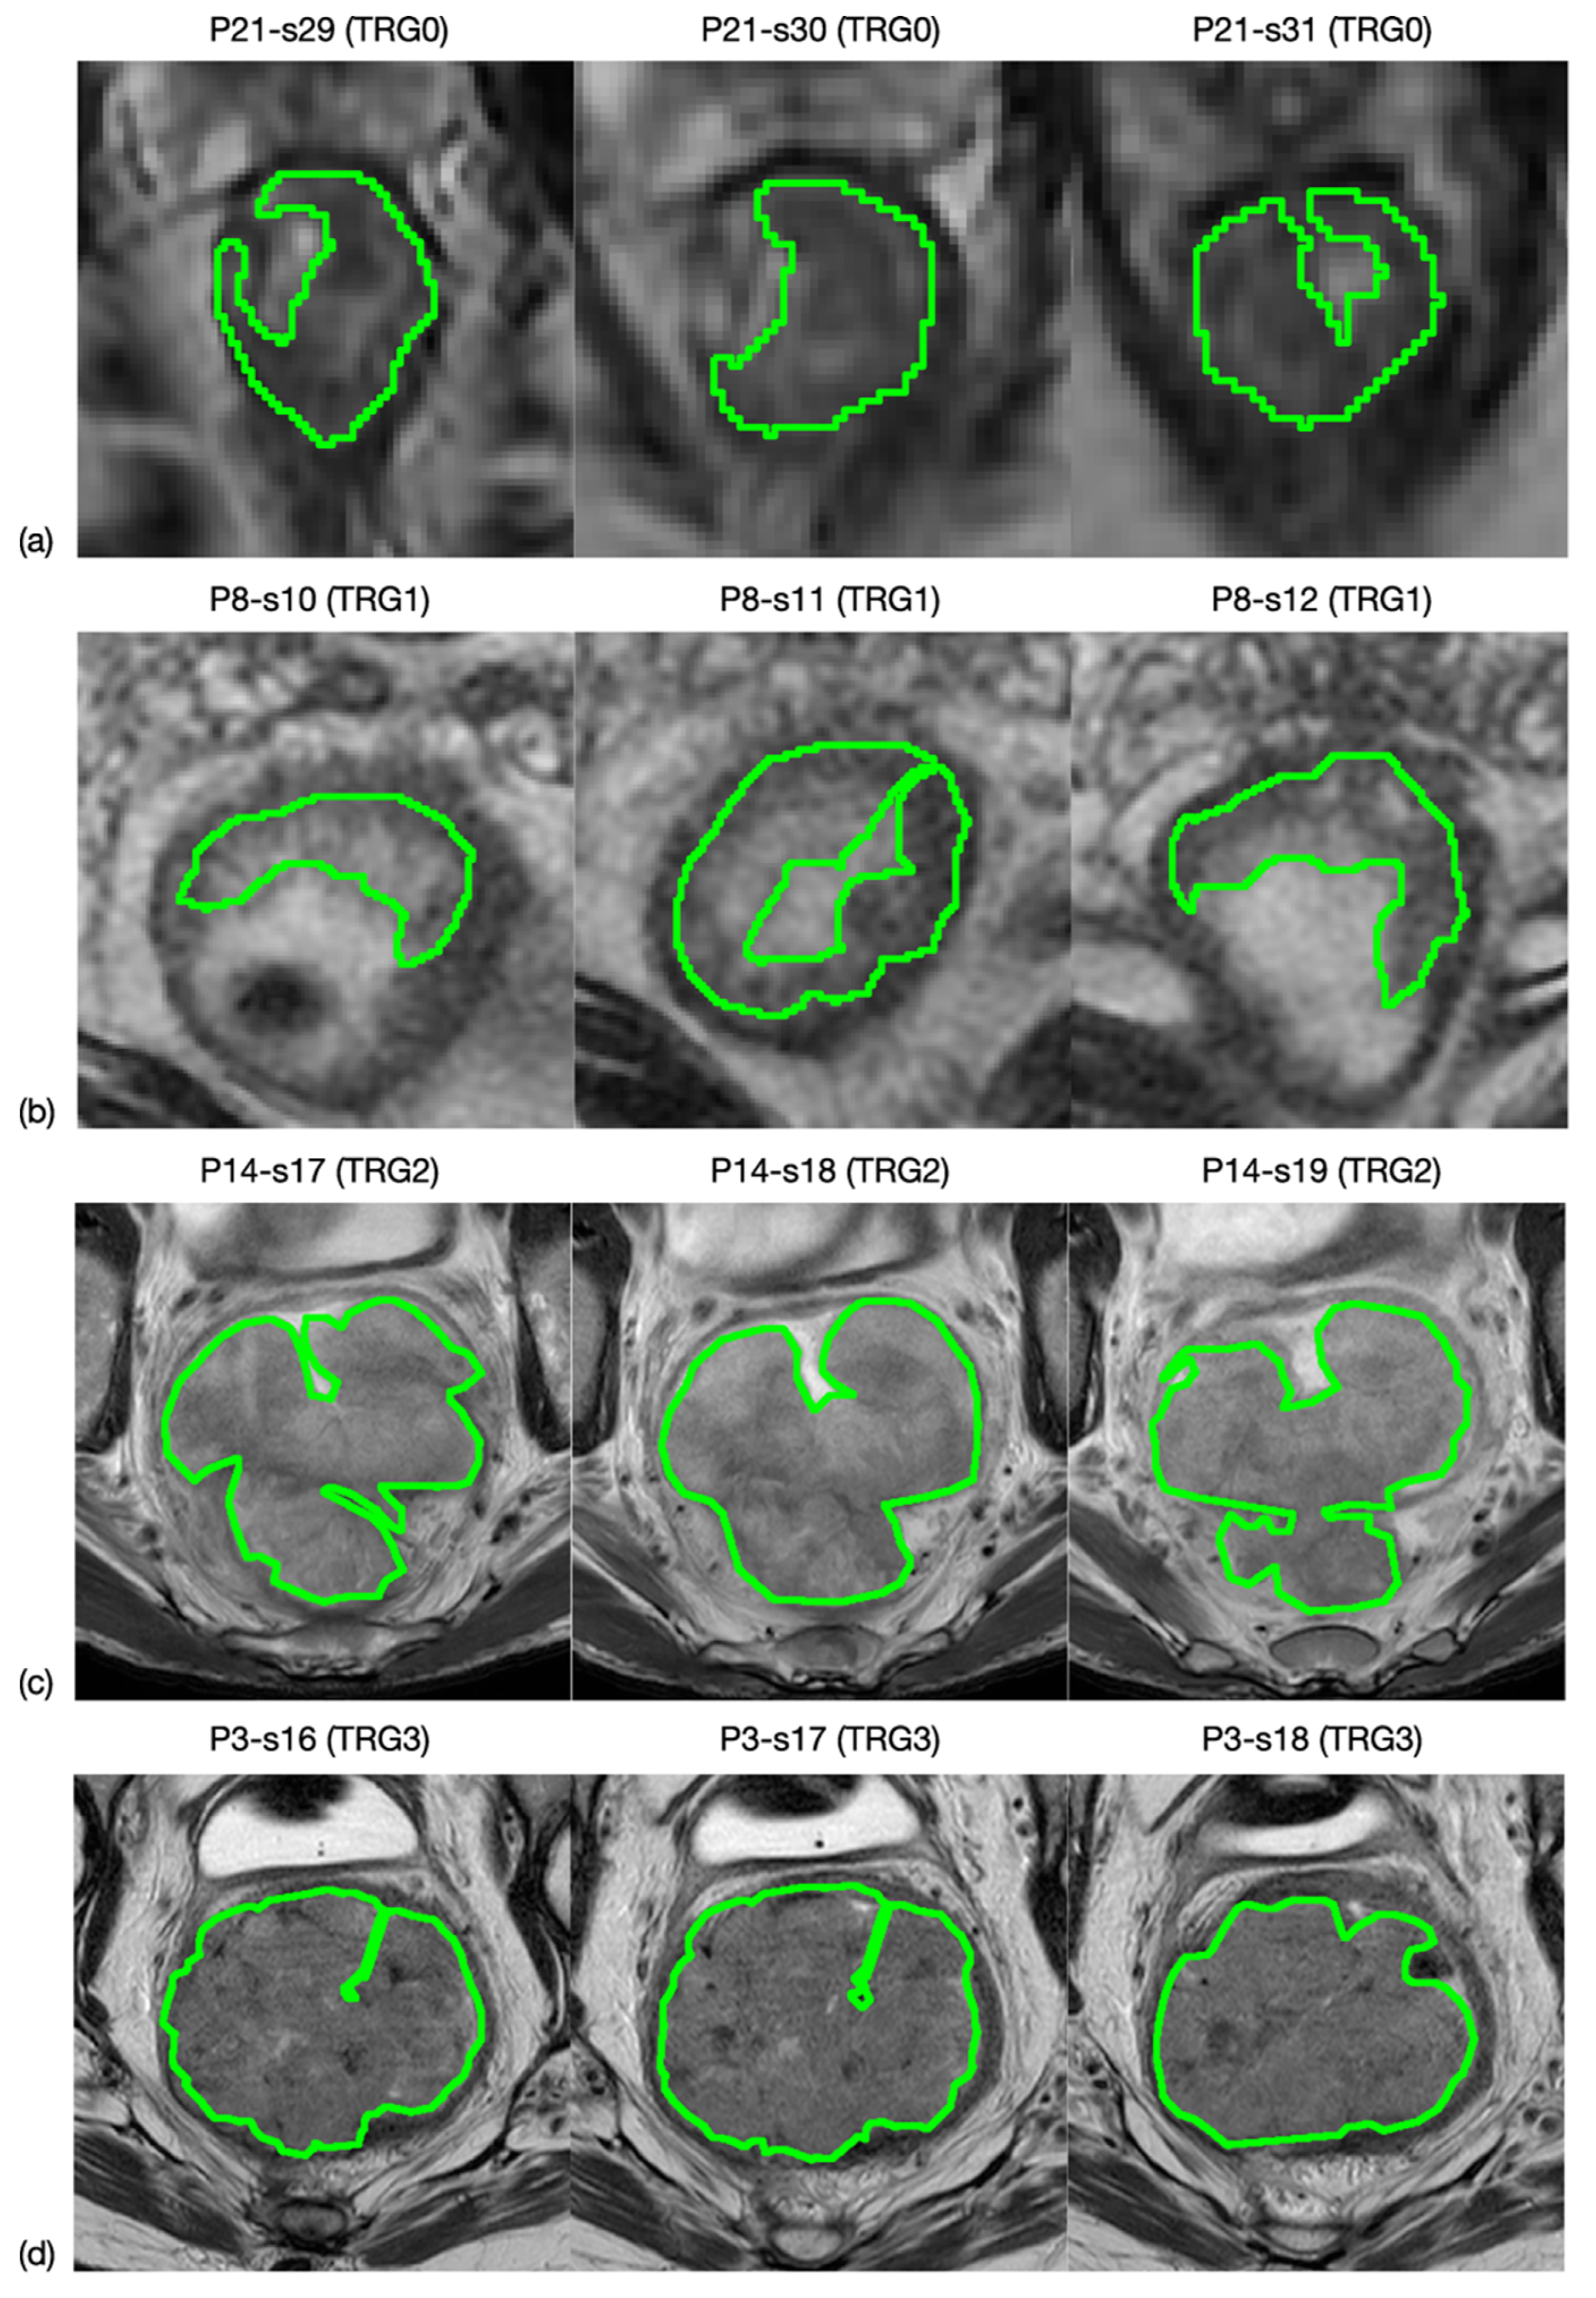

All oblique-axial high-resolution T2w FSE and DWI images were retrieved from the Picture Archiving and Communication System (PACS) (Carestream, Concord, ON, Canada) for image segmentation. A radiologist with more than 15 years of experience (FC) performed all the segmentations by manually outlining the lesion on each consecutive slide—excluding the intestinal lumen—using a designated, free, open source software package for visualisation and medical image processing (ImageJ, version 1.52a, available at https://imagej.nih.gov/ij, accessed on 9 November 2020) [19]. This was performed in two stages: (1) the entire tumour region was highlighted on 3 orthogonal planes of the space and (2) manual segmentation was performed on the 3 mm-thickness axial plane in all slices of the tumour site, by outlining a region of interest (ROI) for each of them. An example is shown in Figure 1. The radiologist was blinded to the histopathological results.

Figure 1.

MRI image segmentation. Here is reported an example of how the segmentation process was carried out. In particular, line (a) shows three slices selected from an MRI study of a patient whose rectal cancer presented a TRG0 in the pathological study, while lines (b–d) correspond to TRG1, TRG2 and TRG3.